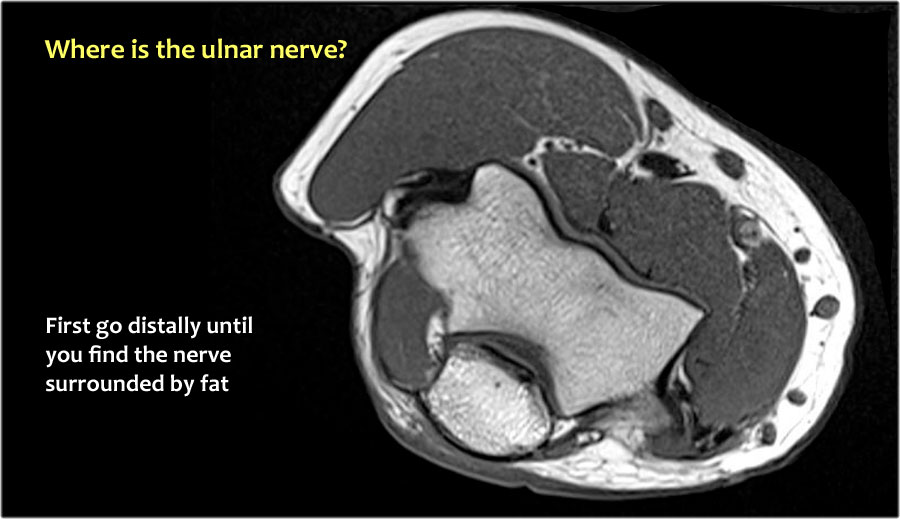

Vì vậy, khi chúng ta quay lại hình ảnh, bạn sẽ nhận thấy rằng có thể khó tìm thấy dây thần kinh.

Bất kỳ cấu trúc dưới da nào trong số này đều có thể là dây thần kinh đã được chuyển vị.

Một cách để thực hiện là đi theo các cấu trúc về phía xa cho đến khi tìm thấy dây thần kinh trụ ở phía xa tại vị trí bình thường của nó ở vùng cẳng tay gần được bao quanh bởi mô mỡ.

Sau đó khi bạn theo dõi nó về phía gần, bạn sẽ nhận thấy rằng đây là một trường hợp chuyển vị dưới da.